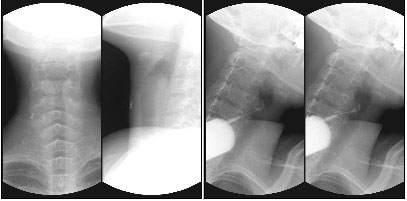

기타 조영 검사 - Swallowing test